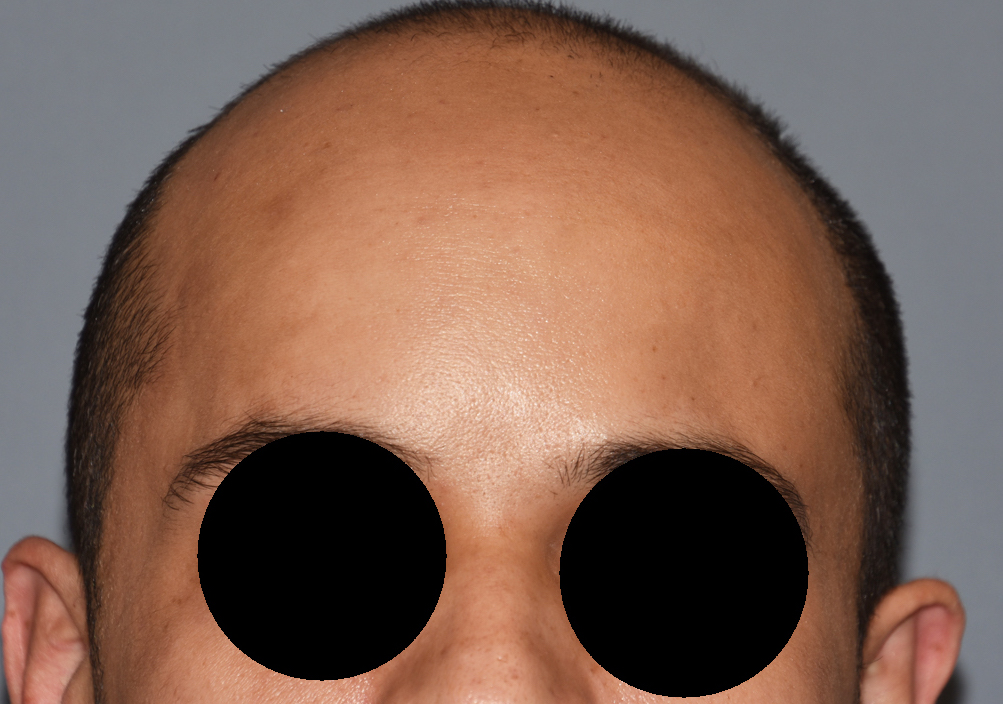

Patient 100

Desire for reshaping of an asymmetric flat back of the head in a shaved head male.

A combined back of the head reshaping procedure was done with a custom skull implant, sagittal ridge reduction and a right temporal muscle reduction.

Desire for reshaping of an asymmetric flat back of the head in a shaved head male.

A combined back of the head reshaping procedure was done with a custom skull implant, sagittal ridge reduction and a right temporal muscle reduction.